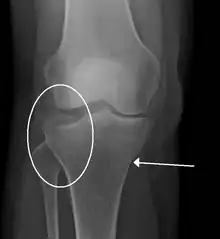

Lipohemarthrosis (presence of fat and blood from bone marrow in the joint space after an intraarticular fracture) seen on X-ray in a person with a subtle tibial plateau fracture

Lipohemarthrosis due to a tibial plateau fracture